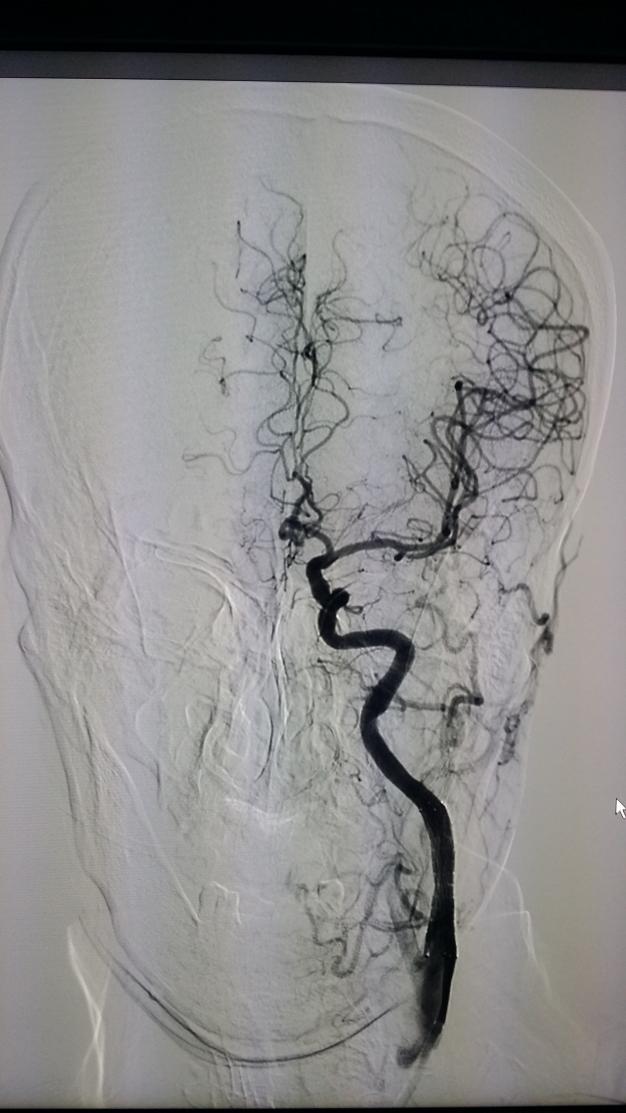

颈动脉支架手术示例:

正位: 术前 支架植入后